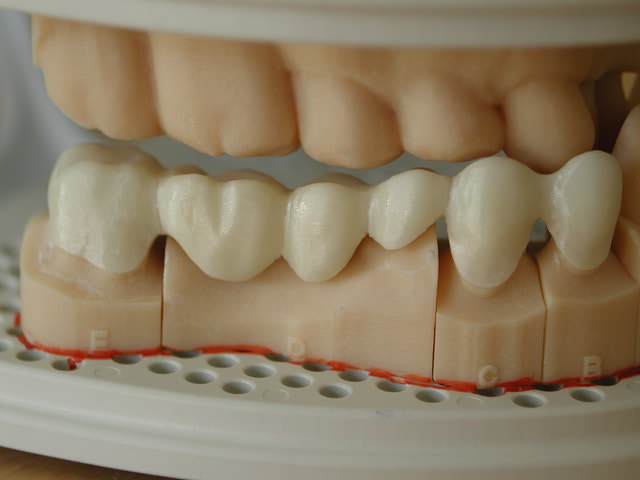

J'ai le plaisir de vous présenter un cas clinique de couronne E-Max sur 22 réalisé à partir de l'empreinte optique intra-buccale.

j'attends encore quelques photos de la CAO de leur part pour mettre à jour l'article mais je voulais déjà vous faire profiter de "ma partie"...